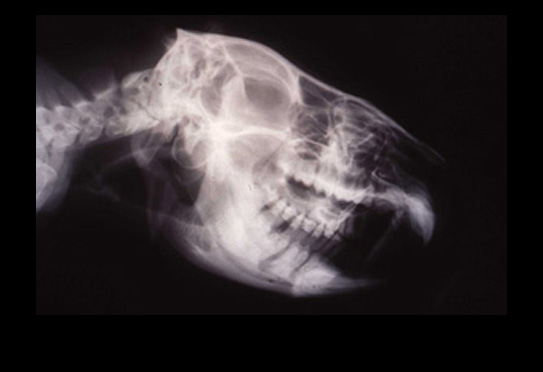

The WEDGE® is a one-piece, radiolucent mouth prop. The patented, anatomic design holds the carnivore mouth open during anesthesia by securely engaging the premolars and molars.

"The (Scheels) Veterinary mouth prop's biggest asset is its simplicity - open the mouth and stick it in!...it does not interfere with radiographic detail, can be ultrasounded, and autoclaved...can be used for dental and oral surgery procedures...is positioned within the mouth, unlike the spring loaded (extra-oral) devices which can be in the way of the operator and interfere with positioning the patient..."